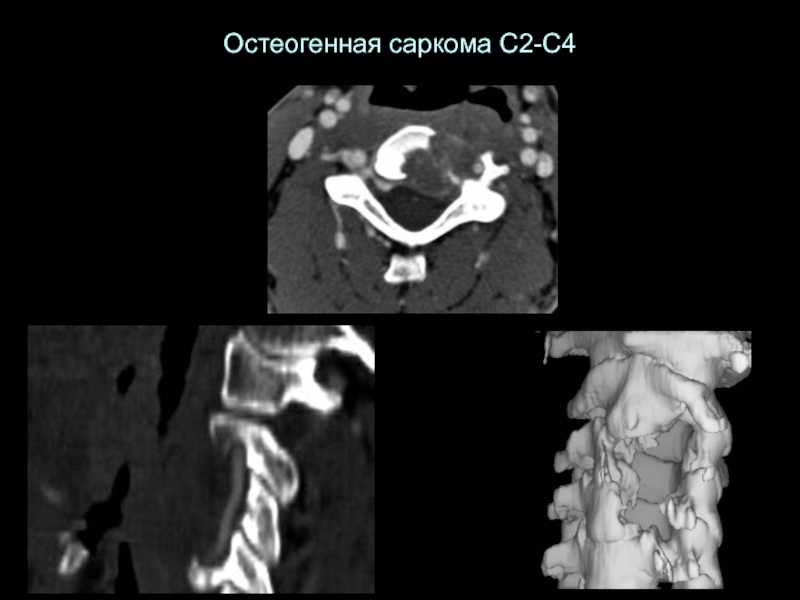

Слайд 30Остеогенная саркома С2-С4

Остеогенная саркома С2-С4